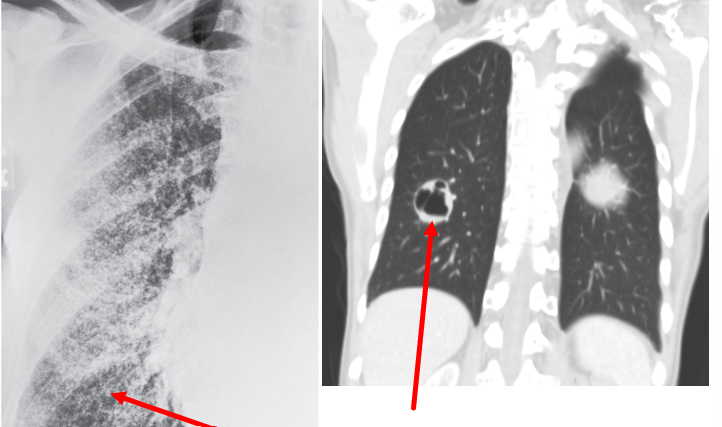

What pathology does the following CxR represent?

A

Cavitation caused by Miliary TB

What TB Outcomes are expected from the resulting Structural changes: Cavitation?

- Visible on CxR, seen as tissue destruction by granulomas (immune cells) - Higher bacterial loads - Risk of hemoptysis (coughing blood) - Increased WOB